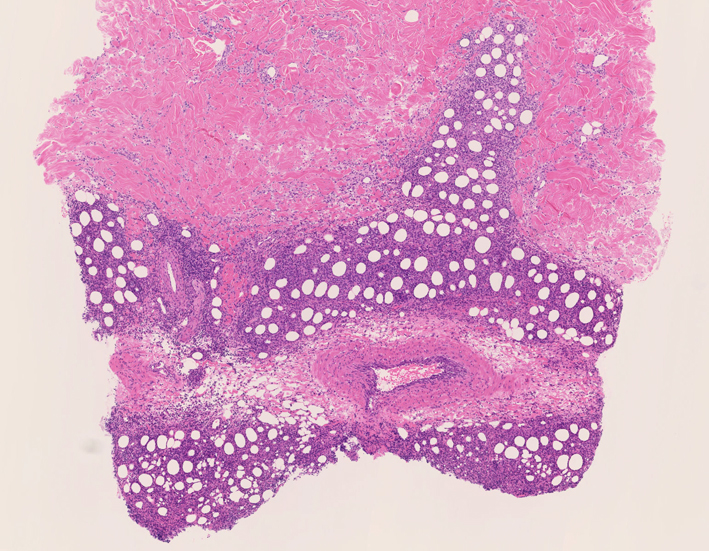

リンパ腫の定義: SPTCLは成熟細胞障害性T細胞(cytotoxic T-cell)由来で、皮下組織に脂肪識炎に似た組織像を呈しながら増殖する悪性リンパ腫。

皮膚生検組織 サムネイルをクリックすると大きな画像がみられます。

組織所見*16*17*18

皮下組織に優位な, 小~中型 Tリンパ球の密な浸潤が特徴。ときに大型リンパ球や組織球が混在する。 リンパ球の異型は, わずかなものから明瞭な異型を示す症例までさまざまである。